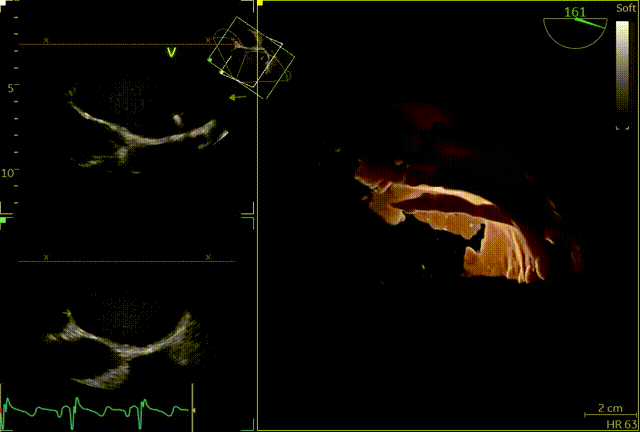

释放后

外侧2偏1区可见后叶栓系,下方空间乳头肌腱索杂多,后叶长度也一般,跨瓣压差3mmHg,第三枚夹子选择了NT,打算靠近第一枚夹子2偏1区夹持,置入NT后,在1区上方做轨迹测试,充分释放张力,调整夹子的夹臂方向位于1点-7点的方向,回拉系统,使第三枚夹子靠近第一枚夹子,关小夹子进入到心室侧,由于第一枚夹子起到了稳定瓣叶的作用,第三枚夹子捕捞夹持相对顺利,一次精准捕获前叶和后叶,再次完整评估二尖瓣NT的方向、组织桥稳定性、瓣叶受限程度及反流减小程度。反流改善到1+-2+,平均跨瓣压差3.85mmHg,左房压明显下降,肺静脉逆流明显改善,手术完美结束。

第三个夹子NT

最终结果

术后肺静脉频谱

术后平均跨瓣压差

术后左房压